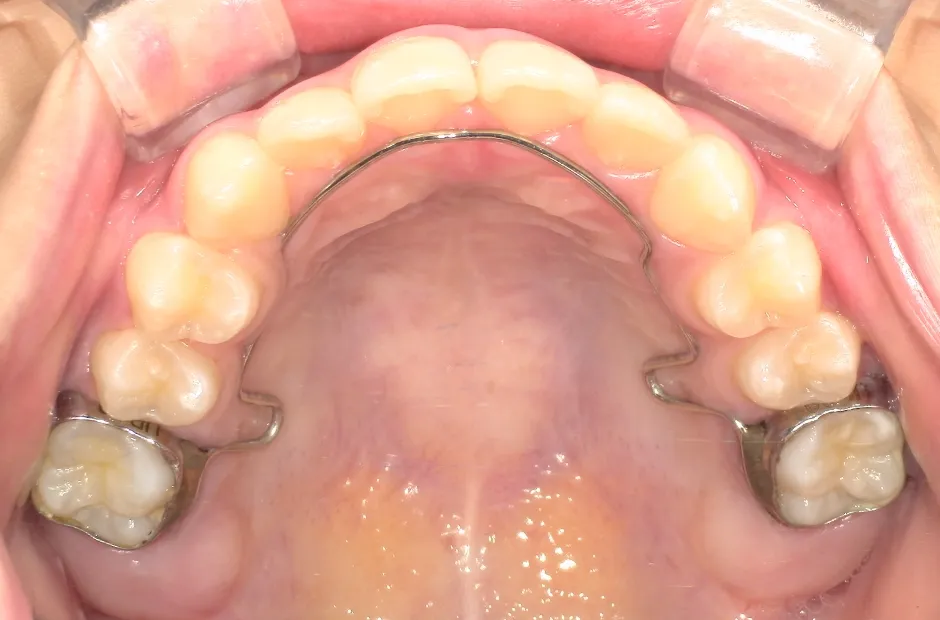

歯列矯正用ワイヤー

主に前歯数本の噛み合わせが逆になっているケースの改善で使用する装置です。左右の奥歯にバンドを固定し、それを支えとして歯列の内側に沿うようにワイヤーを通すことで、ワイヤーの弾力で特定の歯の傾斜を改善します。